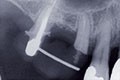

Les examens cliniques et radiographiques montrent une parodontite chronique généralisée (fig. 1a à m).

Nous décidons d’entreprendre une thérapeutique initiale parodontale classique dans tous les secteurs, y compris l’extraction de 24, un bridge de 45 à 48 avec 46 en pontique, un bridge complet de contention de 17 à 27 sur 11 piliers dentaires et une greffe épithélio-conjonctive sur 31. Cette dernière ne sera jamais réalisée. Le bridge maxillaire permettra de réduire le surplomb antérieur et d’améliorer le sourire de la patiente, ce qui constitue l’une de ses demandes.